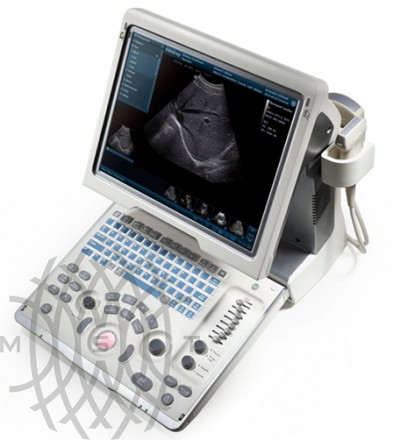

Портативный ультразвуковой аппарат Mindray DP-50

Mindray DP-50 - цифровая черно-белая ультразвуковая система портативного типа, оснащенная жидкокристаллическим широкоугольным монитором с диагональю 15 дюймов и возможностью изменения наклона для улучшения обзора и удобства врача. УЗИ сканер может работать от аккумулятора, а также от сети. Отличаясь компактными габаритами и имея сравнительно небольшой вес (всего 7,5 кг), легко размещается в помещениях с ограниченным пространством.